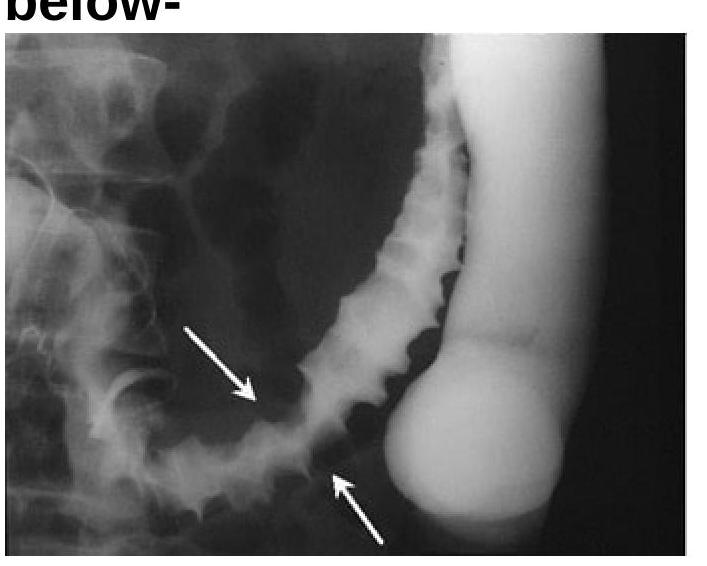

Question 8: Identify the radiological sign of Ischemic colitis from the image provided.

- C. Thumbprinting sign of Ischemic colitis (Correct Answer)

Explanation: ***Thumbprinting sign of Ischemic colitis*** - The image displays prominent **indentations (thumbprinting)** along the bowel wall, especially in the descending colon (indicated by arrows). These indentations are caused by **edema** and **hemorrhage** in the submucosal layer due to ischemia. - This characteristic appearance on a barium enema or CT scan is a classic radiological sign highly suggestive of **ischemic colitis**. *Diverticulitis* - Diverticulitis typically presents with **saccular outpouchings** (diverticula) that become inflamed, potentially showing wall thickening or **pericolonic fat stranding**. - This image does not show typical diverticula or signs of severe inflammation associated with diverticulitis, but rather diffuse mucosal changes. *Appendicitis* - Appendicitis is characterized by inflammation of the **vermiform appendix**, typically seen as a **dilated**, non-compressible appendix with surrounding fat stranding in the right lower quadrant. - The radiological findings in the image are of the colon, not the appendix, and are inconsistent with acute appendicitis. *None of the options* - The image presents a clear and characteristic radiological sign that points to a specific diagnosis, making this option incorrect. - The presence of **thumbprinting** is a well-established indicator for ischemic colitis.